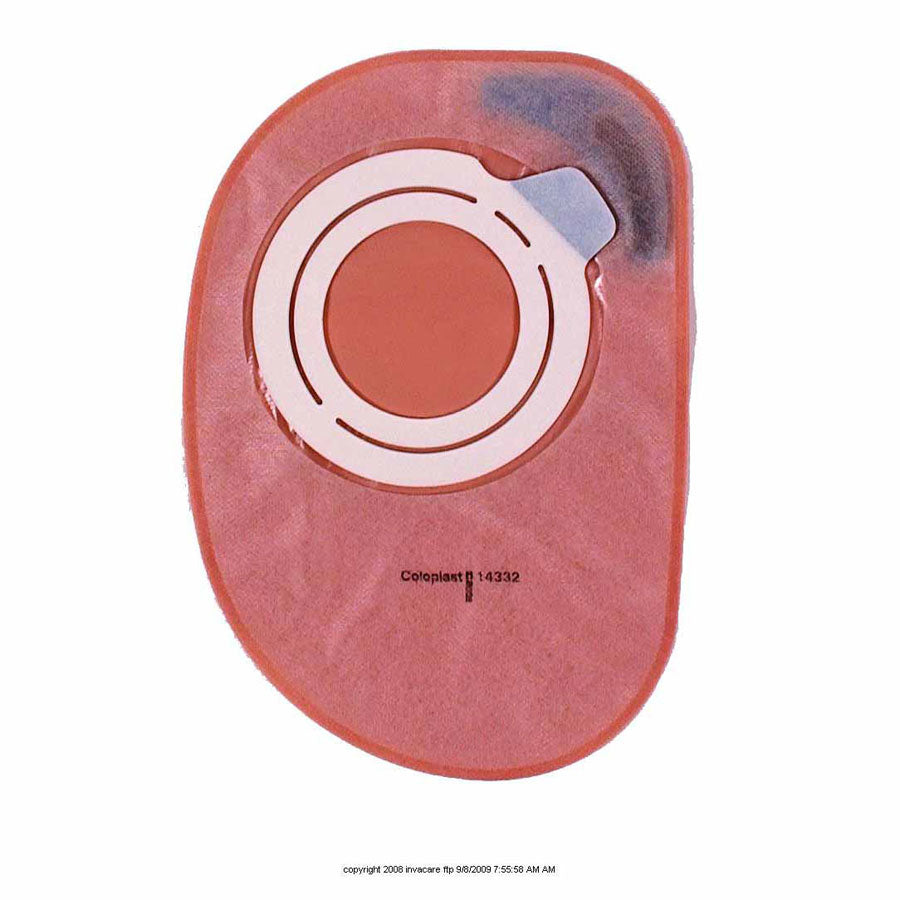

Soft, moisture-absorbent backing, filter for odor control. Opaque. Length: 10 1/2" (26.5cm) / 850mL. Latex Free. Color Code: Grey.